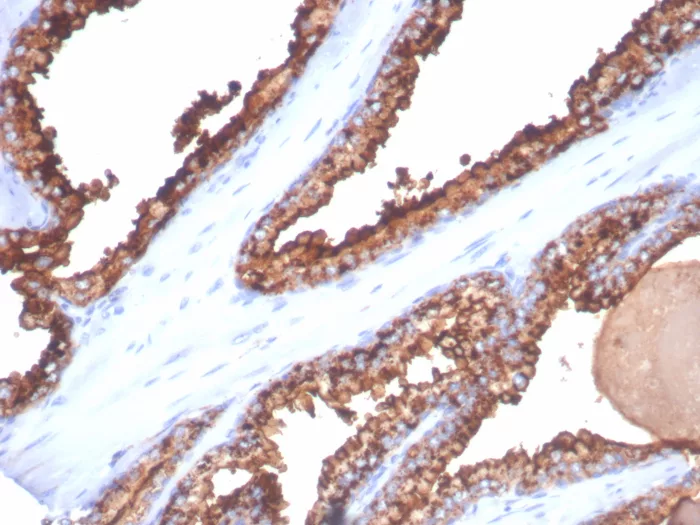

Formalin-fixed, paraffin-embedded human kidney cancer stained with CD26 Mouse Monoclonal Antibody (DPP4/7415). HIER: Tris/EDTA, pH9.0, 45min. 2°C: HRP-polymer, 30min. DAB, 5min.

Recognizes a glycoprotein of 110kDa, identified as CD26 (Workshop VI; Code: N-L039). It is an atypical serine protease belonging to the prolyl oligopeptidase family. It is expressed on lymphocyte cells and is upregulated during T-cell activation. CD26 is also expressed on activated B cells and natural killer cells and abundantly on epithelia. CD26 is implicated in a variety of biological functions including T-cell activation, cell adhesion with extracellular matrix such as fibronectin or collagens, and in HIV infection. Cross-linking of CD26 using this antibody dramatically enhances the anti-CD3-induced IL-2 production. In Western blotting, this MAb reacts with only glycosylated CD26, but not with the deglycosylated form. It does not prevent ADA binding to CD26.